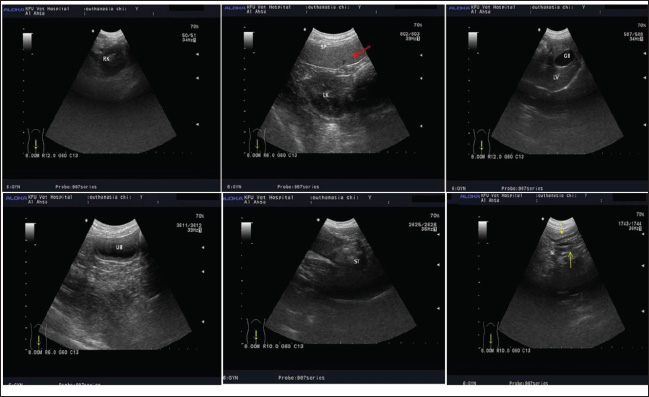

In the illustrated Figure 1, organ boundaries are clearly distinguishable before death; however, following euthanasia, tissue echogenicity diminishes as blood pools in the lower regions, resulting in reduced tissue vitality. This pattern was even observed in the early postmortem period (group 0), when PMI was reported as less than 24 hours. Between-group comparisons of mean echogenicity values showed that there was only a significant difference in the liver echogenicity among groups 0, 2, and 4 hours postmortem. Ultrasound could distinguish the antemortem and postmortem ultrastructure (Table 1)

Fig. 1. Identification of antemortem features of internal organs in dogs under light anesthesia with wide normal small and large intestines and the presence of cleared splenic blood vessels that could be easily identified by ultrasound imaging.